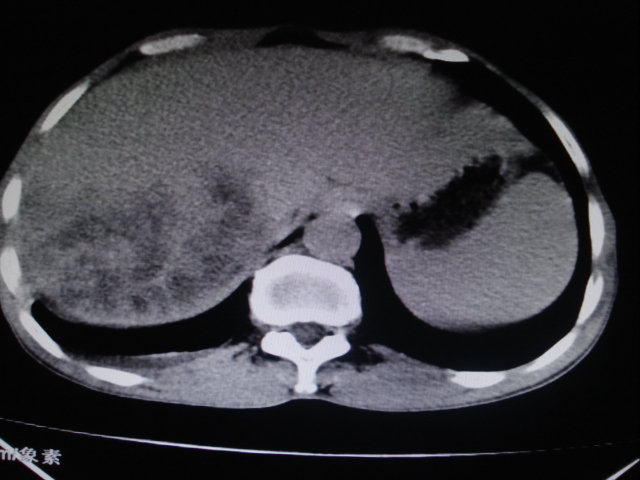

标题: CT24041:肝脏占位,请会诊!

男性,62岁。肝右叶占位,平扫及增强如下,延迟期为15分钟扫描。